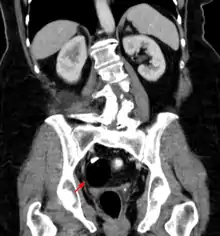

Beyond the newborn period, symptoms of a teratoma depend on its location and organ of origin. Ovarian teratomas often present with abdominal or pelvic pain, caused by torsion of the ovary or irritation of its ligaments. A recently discovered condition where ovarian teratomas cause encephalitis associated with antibodies against the N-methyl-D-aspartate receptor antibody (NMDAR) - often referred to as "anti-NMDA receptor encephalitis", was identified as a serious complication. Patients develop a multistage illness that progresses from psychosis, memory deficits, seizures, and language disintegration into a state of unresponsiveness with catatonic features often associated with abnormal movements, and autonomic and breathing instability.[34] Testicular teratomas present as a palpable mass in the testis; mediastinal teratomas often cause compression of the lungs or the airways and may present with chest pain and/or respiratory symptoms.